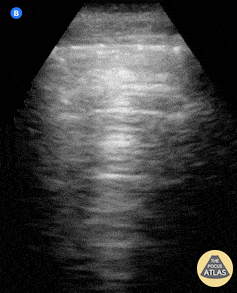

Pulmonary - Normal lung

Lung ultrasound of a normal lung. Note both lung slide (shimmery, hyperechoic line on top of the screen, a result of parietal and visceral pleura sliding against each other) as well as multiple parallel A-lines (normal artifact from reverberation of the pleural line). The presence of lung sliding and no more than 3 B lines on lung ultrasound help exclude inersitital pulmonary edema and pneumothorax. Shahad Al Chalaby, MD. PGY-2, Internal Medicine Highland Hospital, Alameda Health System Internal Medicine Residency Program. CA, USA @shahad_Chalaby